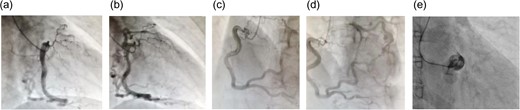

A 62-year-old woman presented with exertional chest pain. She visited our hospital because her symptoms were gradually intensifying for several years. Her only risk factor for heart disease was hypertension; she had no history of smoking, and she did not have dyslipidemia. Electrocardiography did not show any ischemic changes. On echocardiography, left ventricular function was preserved and neither hypokinesia nor valvular heart disease was observed. Further evaluation of coronary artery disease was considered necessary; therefore, she underwent a detailed examination using coronary computed tomography (CT) (Fig. 1), which revealed an LMT occlusion. Coronary angiography also revealed that the LMT was occluded at the origin. The entire left coronary artery was visualized through collateral circulation in right coronary angiography (Fig. 2). Based on blood test findings and aortic CT results, arteritis and autoimmune disease were ruled out.

Coronary angiography at the time of the initial diagnosis. (a and b) Anterior-left lateral image and (c) posterior-right lateral view. The disruption of blood flow to the LMT can be seen. Despite this disruption, the left anterior descending coronary artery and the circumflex artery demonstrate contrast enhancement. There is no indication of calcification or other lesions in the LMT.